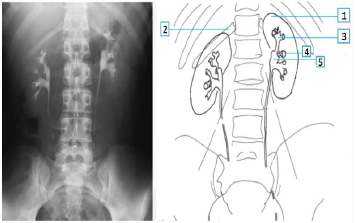

As TCs (Tomografias computadorizadas) são

valiosas em emergências porque são capazes de

fornecer informações muito rapidamente. Isso é

importante, por exemplo, para diagnosticar e analisar

derrames, lesões cerebrais, doenças cardíacas e lesões

internas. A figura que segue mostra uma imagem com

contraste de estruturas renais.

Os números 2, 4 e 5 da imagem à direita, se referem, respectivamente à: